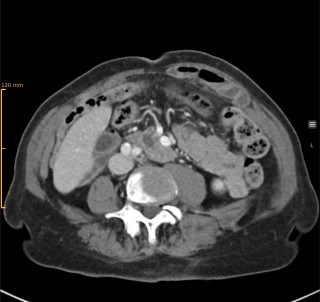

Twenty (n=20) consecutive patients undergoing pancreatic resection were prospectively enrolled. In addition, n=10 patients undergoing other major abdominal surgery served as control group. Dexcom G6 CGM system was used. Time in euglycemic range (TIR) and peak glucose levels were analyzed. Routine serum glucose measurements and daily C-reactive protein (CRP) levels were also assessed. Comprehensive Complication Index (CCI) was used to quantify postoperative complications.

Results

No adverse events related to CGM devices were observed. Glucose levels increased significantly from a median of 7mmol/l (IQR 6-8mmol/l) to 9 mmol/l (IQR 8-1mmol/l, P=0.026) after pancreatic resection. Correspondingly, the TIR decreased from 86.5% (IQR 85-96%) to 78.1% (IQR 34-89%, p=0.042). Perioperative glucose levels (p=0.623) and TIR (p=0.408) remained unchanged in the control group. Linear regression showed a significant correlation between peak glucose levels on day 1, measured by CGM (R=0.738, p=0.004, Figure 1A), and CRP levels on day 2 (R=0.528, p=0.034, Figure 1B) with CCI. In contrast, routine serum glucose levels did not predict complications.

Conclusion

In this pilot study, peak glucose levels on day 1 after pancreatic resection were associated with adverse events. CGM may be a valuable tool to identify patients at risk of complications.